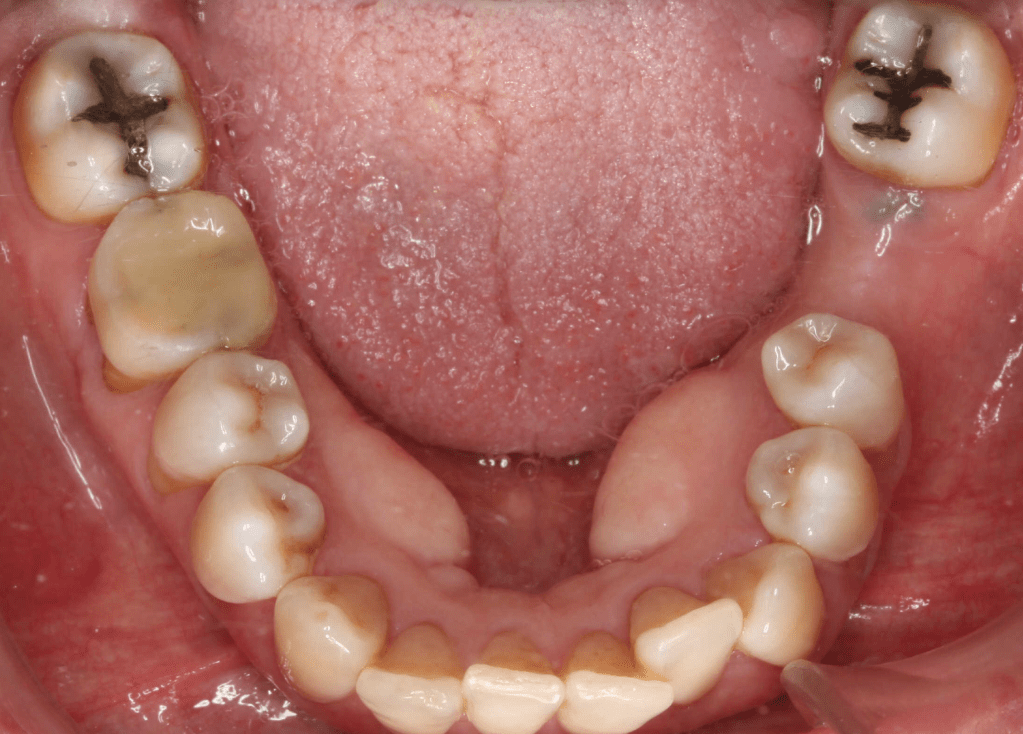

Reco pre-endo, molar inferior